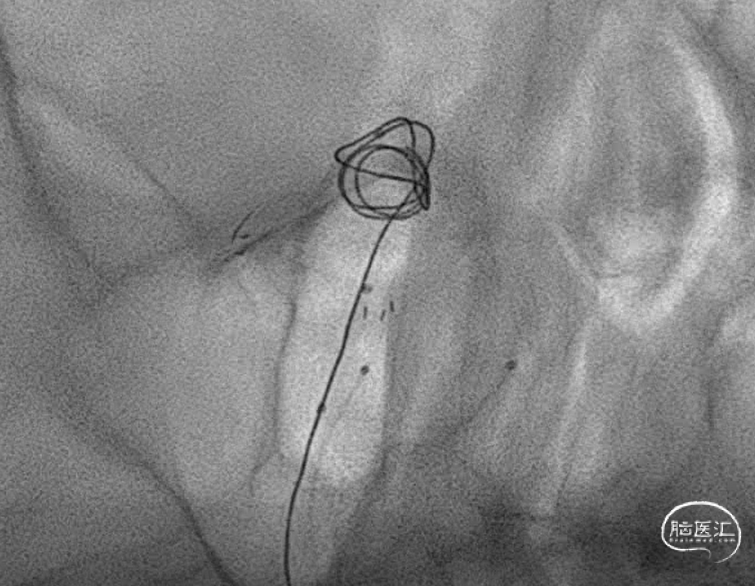

造影显示,左侧大脑后动脉起始似乎还是受到圈的小小影响,最终决定还是把支架放上。

支架释放完毕,感觉还是不太死心,于是调整了微导管几次,由于弹簧圈和支架的阻挡,还是调不进去,如果继续尝试,可能有增加支架内形成血栓的概率和导管可能戳破动脉瘤的风险。于是绝定再造个影看看。

这个角度,感觉残留一些。

换了个角度,感觉还可以。

标准侧位发现,这个位置有些残留,角度还是比较刁的,不太好到位。虽然有这么一点小遗憾。但是从患者是未破裂动脉瘤,及减少患者风险为第一位的角度上看,还是可以考虑一下。因此毅然决定收手。术后患者安好。

静下来想想,有的时候我们追求完美,让手术和患者得到最大的受益无可厚非。但是有的时候能及时收手,减少患者由于增加操作而带来的风险,未尝不是一种正确的选择。仅为个人观点,与诸君分享。同时感谢各位关注。